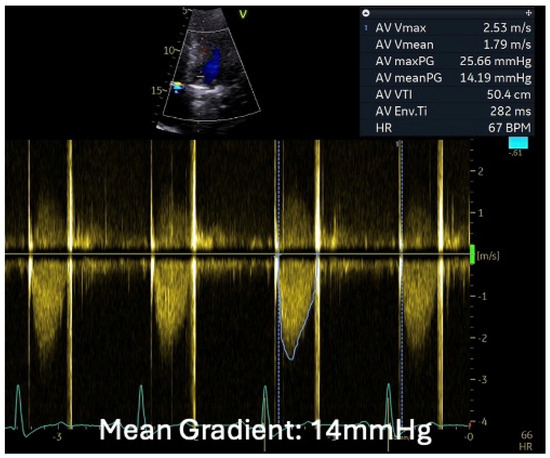

2.3. The Saga of Relapsing IE of the Prosthetic Mitral Valve Causing Structural Valve Degeneration and Transcutaneous MViV Prosthesis